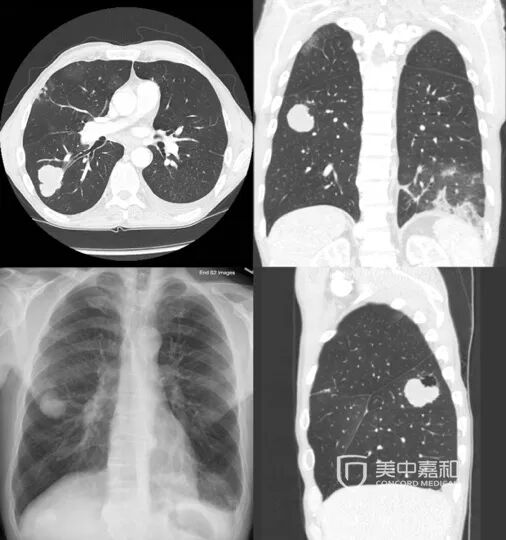

是哪种类型的肺癌?

肺癌主要起源于支气管黏膜上皮,根据病理分型主要包括非小细胞肺癌(NSCLC)和小细胞肺癌(SCLC)。

非小细胞肺癌占所有肺癌类型的 80%~85%[1],如在早期发现,经过治疗可以得到不错的治疗效果;但多数患者就诊时已处于中晚期,失去了手术根治的机会,因而需要采取综合方案进行治疗。

小细胞肺癌占肺癌类型的15%-20%,是起源于神经内分泌细胞的低分化肿瘤,其恶性程度高,相较于非小细胞肺癌,生存率更低。

肿瘤分期如何?是否有转移?

肺癌确诊时的分期是决定预后好坏的关键因素之一。这是因为肿瘤的分期是根据肿瘤的大小、对周围组织器官的影响、淋巴结转移情况、远处器官转移情况等,将肿瘤分为I-IV期。